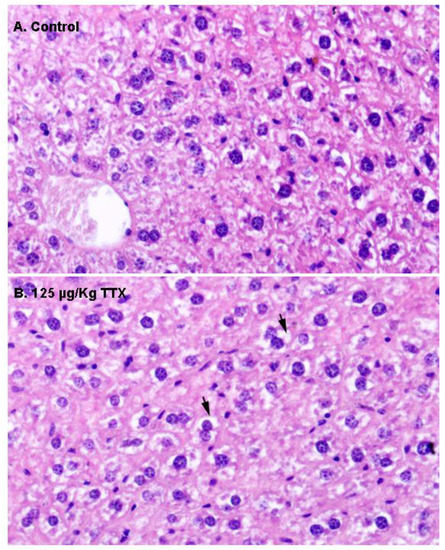

In view of the effects of repeated oral administration of TTX on urine production and the above described alterations in urine parameters, kidney sections from control animals and from mice treated daily with TTX at 125 µg/kg were analyzed next. Figure 4 shows H&E staining of the kidney in control and TTX-treated mice. No evident histological alterations were observed by light microscopy in the kidney of TTX treated-mice.

Finally, as indicate in Figure 6, histological alterations in the heart of control and TTX treated mice were evaluated by light microscopy. Representative images of H&E staining in heart sections of control and TTX-treated mice did not show any evidence of structural alterations in the heart. In both cases, normal cardiac myocytes, which are cylindrical in shape and have an elongated nucleus, were observed.

Figure 4. Kidney sections of a control mouse (left column) and of a mouse treated with 125 µg/kg TTX (right column), stained with H&E (A,B) or PAS (C,D). Renal corpuscules (arrows) and convoluted tubules (CT) are shown in the respective microscope magnifications at 600×.

Figure 6. H&E stained sections of the myocardium by light microscopy. (A) Ventricle of control mouse. (B) Ventricle of a mouse treated with TTX at the dose of 125 µg/kg. Mc: Myocytes. Microscope magnifications of 400× are shown.